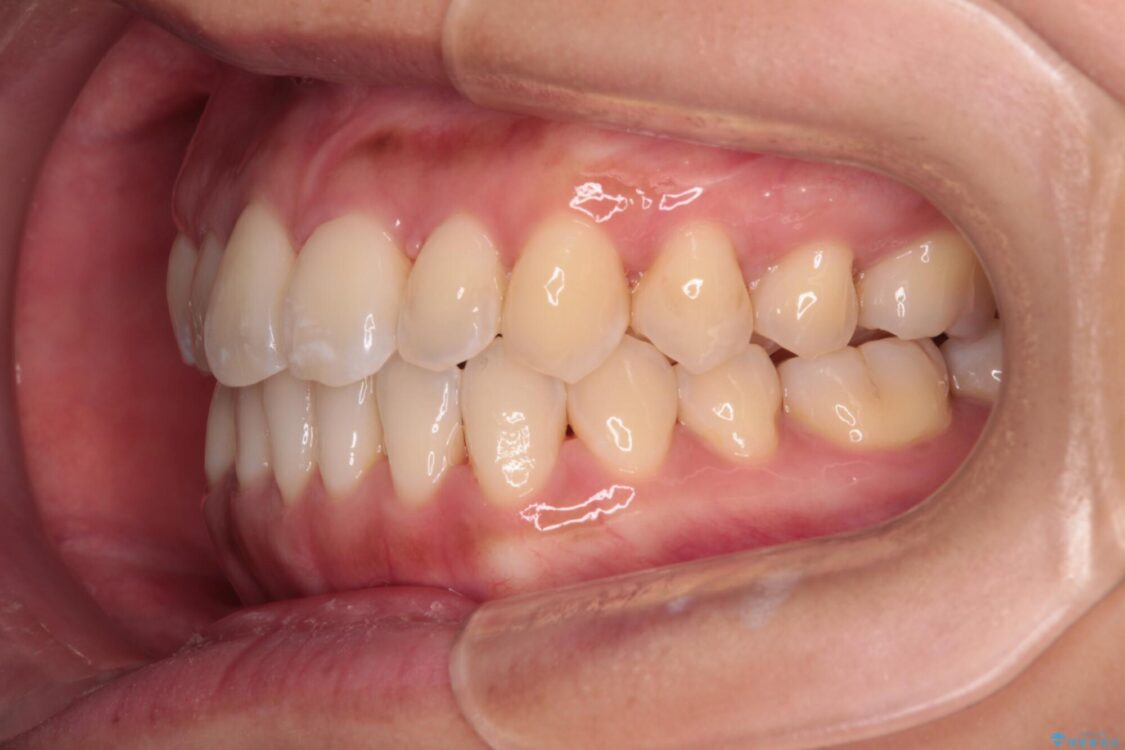

前歯のデコボコで前方に出ていることを気にして来院された患者様です。

上顎前歯が捻れて前方に飛び出しており、下顎前歯もそれに沿うようにデコボコとなっていました。

IPR(歯と歯の間を削る処置)によりスペースを獲得して上下顎前歯のデコボコを改善し、飛び出している前歯が引っ込むように設定し、インビザラインにて矯正治療を行うこととしました。

装着時間を守ってくださったので、予定通りの期間で終えることができました。インビザライン特有の、奥歯の咬み合わせの問題もなく、しっかりと歯列を改善することができました。

治療後

• 【モニター】前歯のデコボコをインビザラインで改善 治療後画像